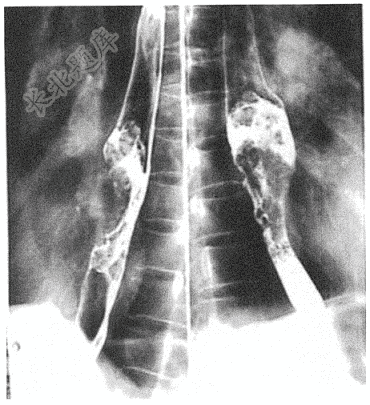

- 简答题患者男性,76岁,主因进行性吞咽困难2个月入院,既往体健。入院查消化道造影如下: